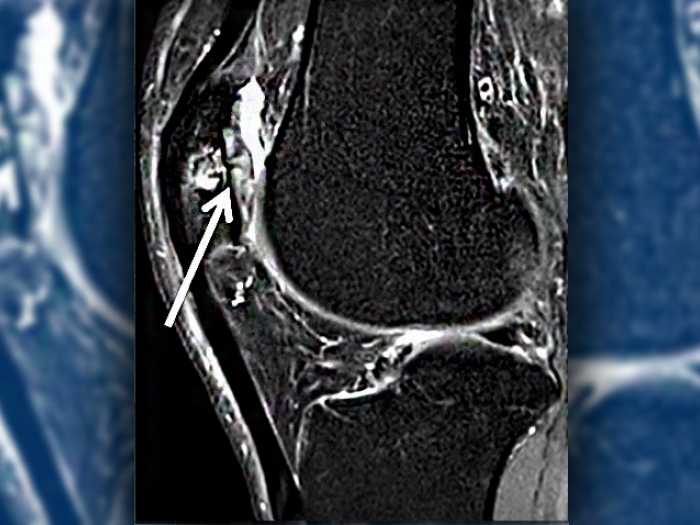

Ultrasound image of knee sag cartilage

Health Lab

A New Option to Rescue Knee Cartilage

A new clinical trial at Michigan Medicine is evaluating a next-generation approach to replacing damaged knee cartilage with healthy cartilage cultivated from a patient’s own cells.

Woman in shorts holding her knee

Knees Hurt? Options for Cartilage-Related Knee Pain

Knee pain can be caused by damaged cartilage.  A Michigan Medicine orthopaedic surgeon describes the current surgical remedies, including a new procedure being tested here.